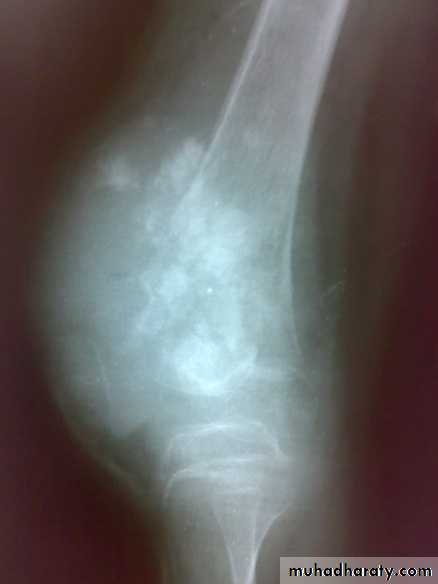

Giant cell tumor

This disease characterized by presence of giant multinucleated cells which seen in large number. The tumor cell is the stromal spindle shape cell.

The tumor is soft and friable occupying the cavity which extend to subchondral region.

Patient presented by local pain and swelling or pathological fractures. Common site is the distal femur, proximal tibia, distal radius.

X-ray show eccentric osteolytic lesion in the end of long bone ,subchondral, trabeculated (soap bubble appearance). The cortex is thin, expanded or even perforated.